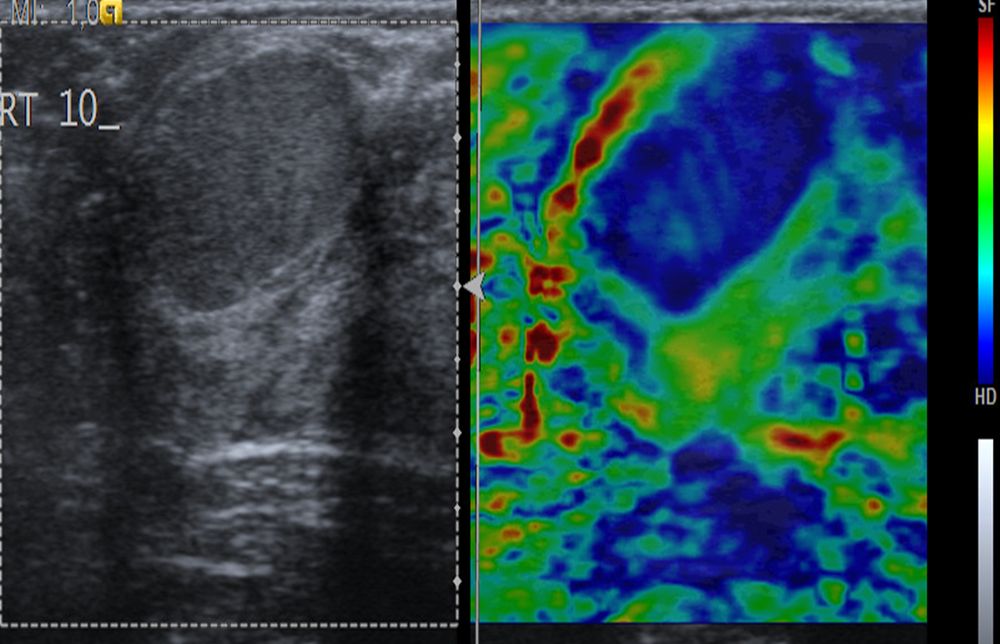

Η ελαστογραφία μαστού είναι μια σύγχρονη υπερηχογραφική μέθοδος που επιτρέπει τη διάκρισητων καλοήθων ογκιδίων από τους κακοήθεις όγκους.

Συνοπτικά ασκείται μια μικρή πίεση στους εντοπισμένους όγκους, μετρώντας την ελαστικότητα τους.

Ο καρκίνος γενικά εμφανίζει μεγαλύτερη σκληρότητα-ελαττωμένη ελαστικότητα σε σχέση με τα καλοήθη ογκίδια και επομένως η ελαστογραφία μπορεί να δώσει τις αναγκαίες πληροφορίες έτσι ώστε να μειώσει τις βιοψίες μαστού μόνο στις απολύτως απαραίτητες.